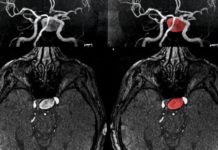

En un nuevo estudio, Christian Benedict, junto a Samantha Brooks, Schiöth Helgi y Larsson Elna-Marie de la Universidad de Uppsala e investigadores de otras universidades europeas, han examinado sistemáticamente que las regiones en el cerebro, que participan en la sensación de apetito, son influenciados por el sueño aguda pérdida. Por medio de resonancia magnética (fMRI), los investigadores estudiaron los cerebros de 12 hombres con peso normal, mientras que ellos veían las imágenes de los alimentos. Los investigadores compararon los resultados después de una noche de sueño normal con los obtenidos después de una noche sin dormir.

Más información: Benedicto C, SJ Brooks, OG O’Daly, MS Almen, A Morell, K Åberg, M Gingnell, B Schultes, M Hallschmid, JE Broman, EM Larsson, y Schiöth H privación del sueño B. aguda mejora la respuesta del cerebro a los estímulos de alimentos hedónico: un estudio de resonancia magnética funcional. Journal of Clinical Endocrinol Metab, en prensa.